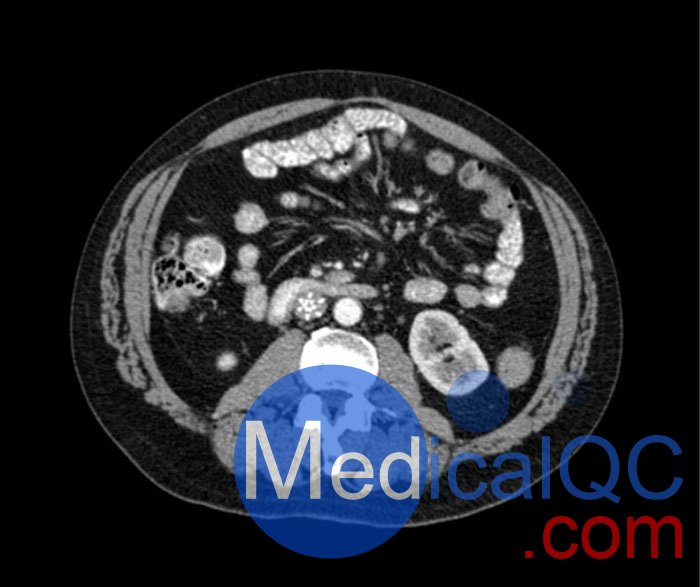

WEK53-04肝硬化腹部模體,WEK53-04門靜脈期腹部模體詳細(xì)介紹:

WEK53-04肝硬化腹部模體,WEK53-04腹部模體模擬了門靜脈期的造影劑增強(qiáng)腹部。它覆蓋了第十胸椎至第三腰椎。

WEK53-04肝硬化腹部模體,WEK53-04腹部模體代表膽囊切除術(shù)后的腹部,帶有小夾子。肝臟有肝硬化的典型體征,在第三腰椎水平植入下腔靜脈過濾器。兩個腎臟都有囊性病變,左側(cè)有一小塊腎結(jié)石。

該模型可用于 CT(包括 CBCT)以評估和優(yōu)化成像性能和后處理應(yīng)用,包括支持 AI 的應(yīng)用。它也適用于培訓(xùn)目的。

該模型提供了對軟組織和骨組織的詳細(xì)而逼真的模擬??障吨刑畛渲s-160HU的纖維素-聚合物復(fù)合材料。

WEK53-04肝硬化腹部模體,WEK53-04門靜脈期腹部模體診斷特征

真實(shí)模擬脈管系統(tǒng)、骨骼和軟組織,包括肝臟、胰腺、脾臟、腎上腺、腎臟、胃、小腸和結(jié)腸。

• 肝硬化

• 膽囊切除術(shù)

• 下腔靜脈濾器

• 腎囊腫

• 腎結(jié)石

• 淋巴結(jié)腫大

WEK53-04肝硬化腹部模體,WEK53-04門靜脈期腹部模體產(chǎn)品成像圖: